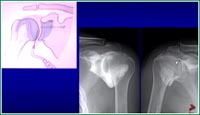

黄公怡:1、肩袖损伤2、肱二头肌腱的长头腱炎3、冈上肌腱的撕裂等是临床最常见的肩部疾病,也是最容易与五十肩相混淆的肩病。冈上肌腱的断裂与年龄有关,如图:年纪大了以后肌腱本身老化、变脆,容易发生断裂。